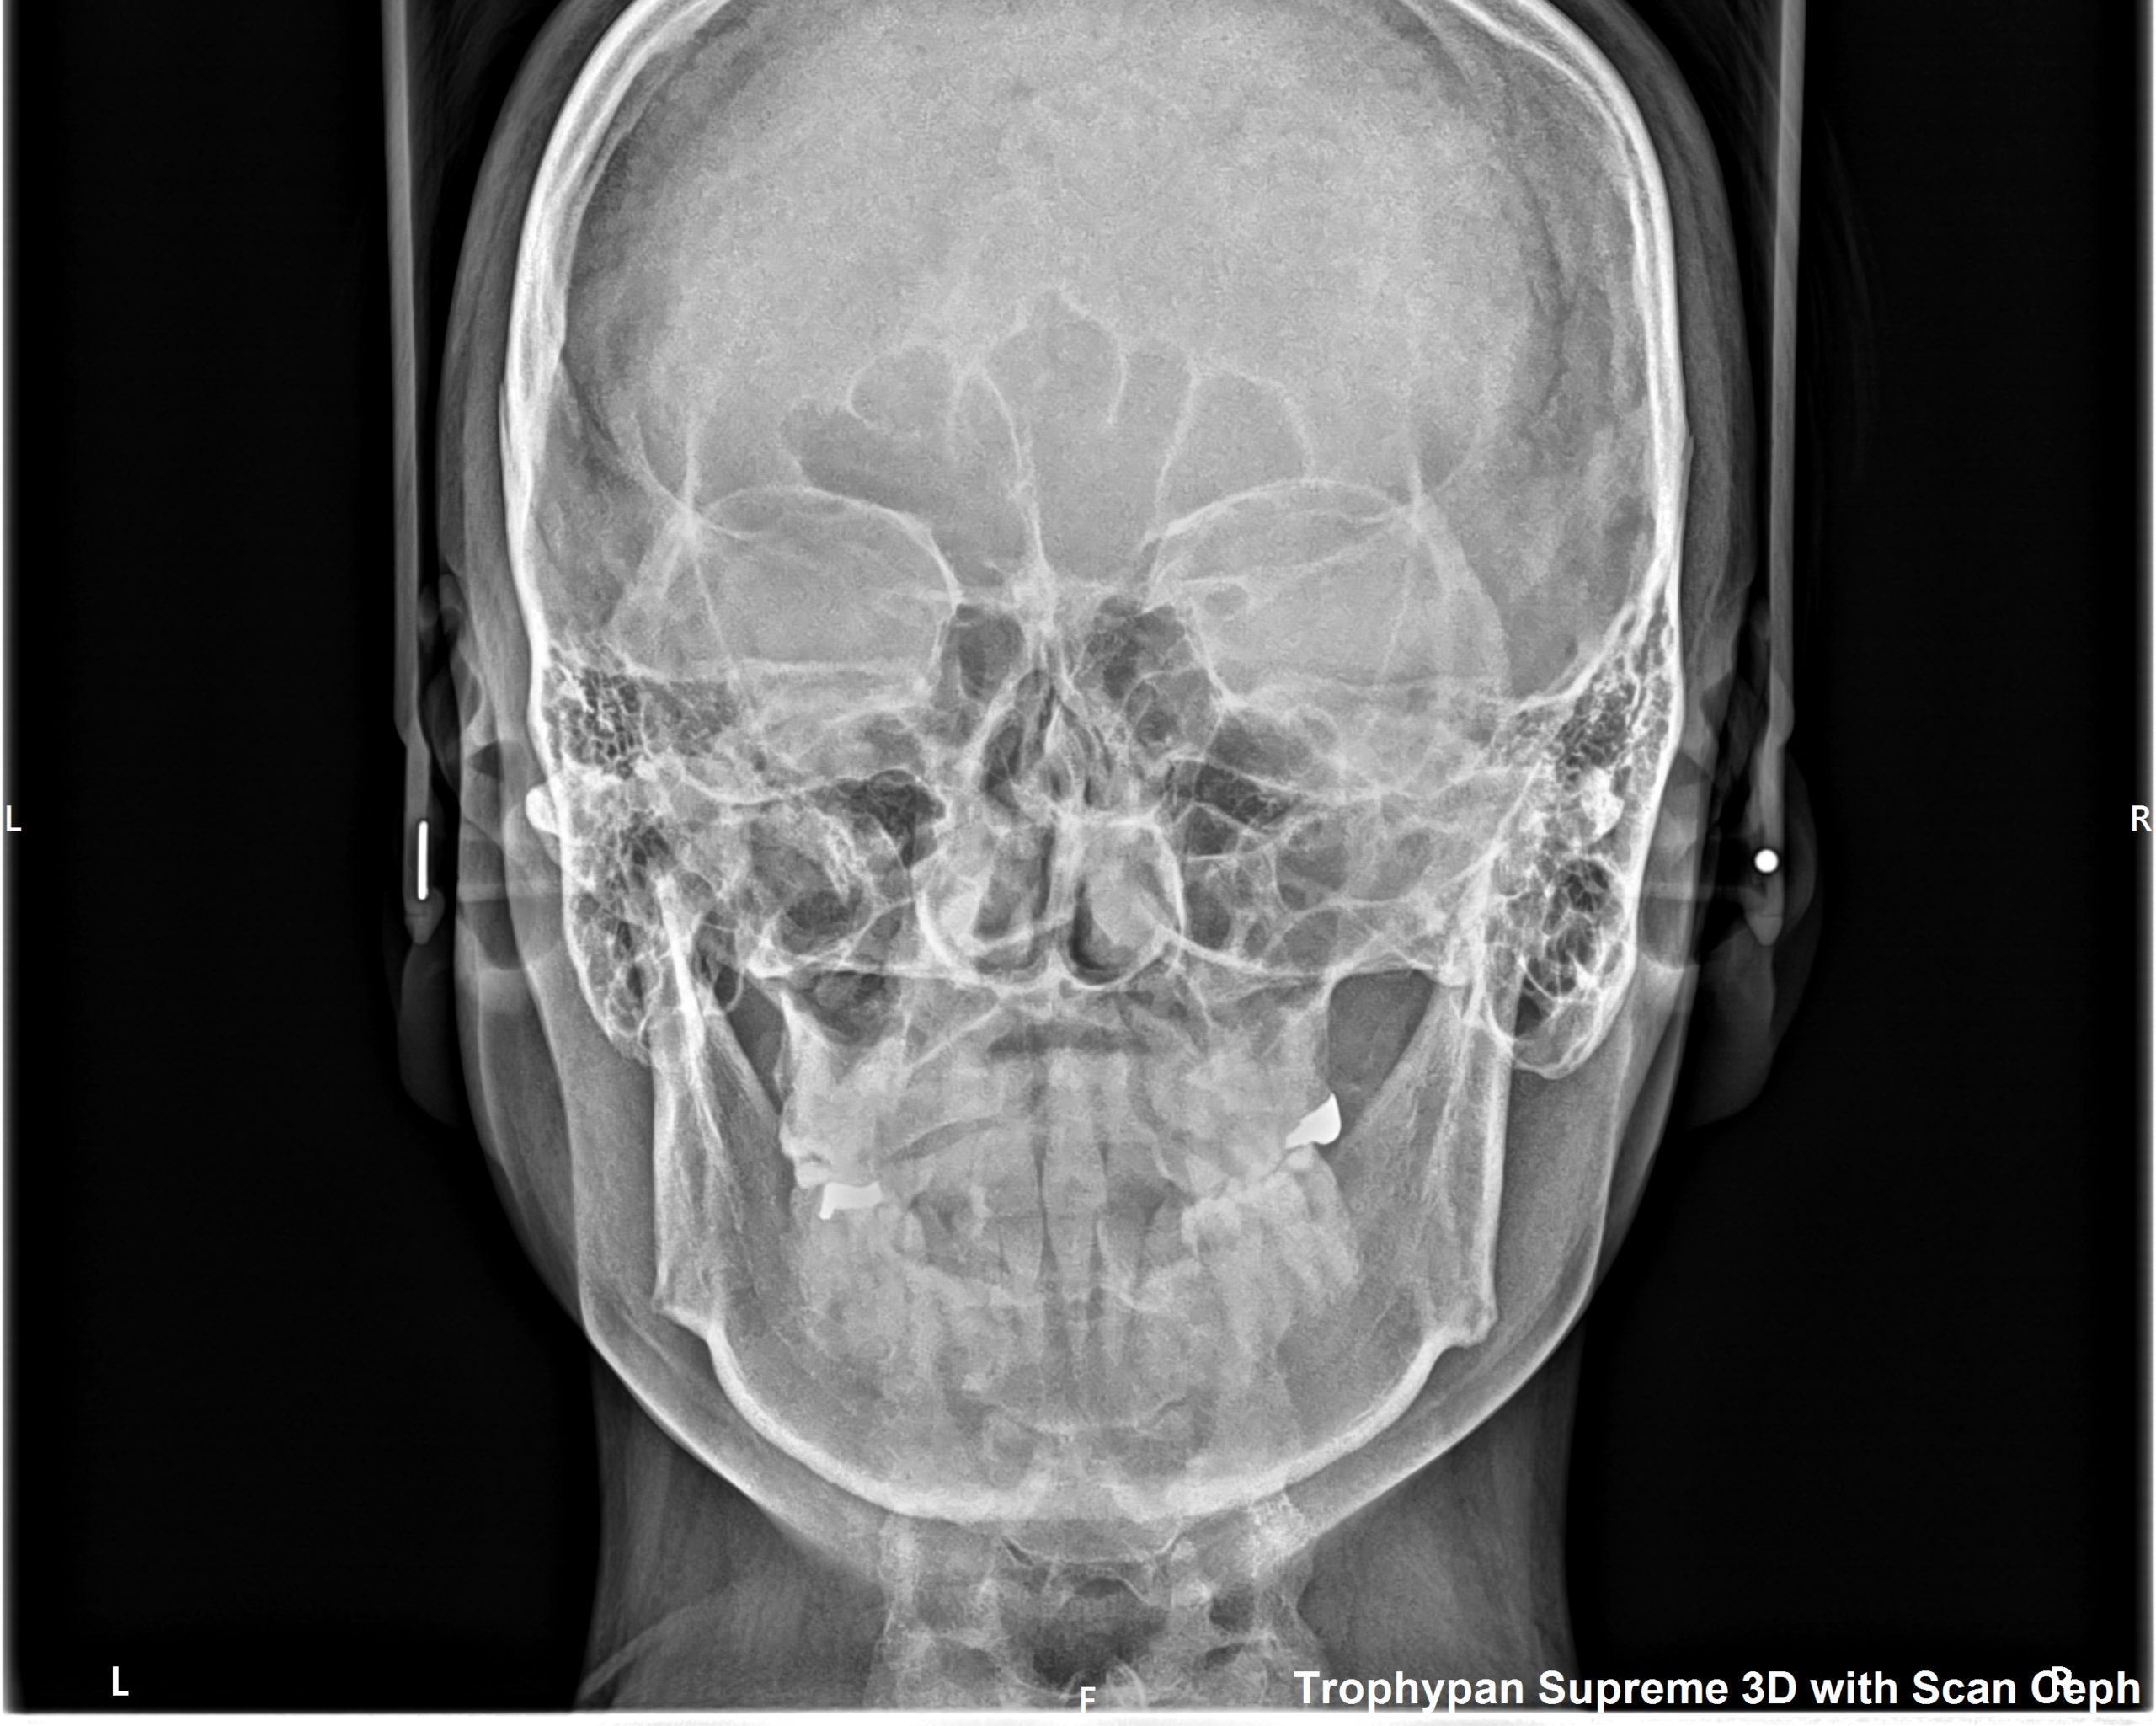

②セファロ写真

側貌写真では、頭部の位置に対する上下顎の前後関係(出っ歯や受け口など)や垂直関係(面長か丸顔かなど)を調べたり、歯の傾きや口元の突出度など様々な要因を数値化して正常値からどれくらい離れているかを確認します。

正貌写真では、正面から見た顔や顎の歪み、前歯の真ん中の位置などを確認します。

当院ではMoon Aligner Systemという診断ソフトを用いて、撮影後3~5分でレントゲン写真から以下の画像のようにAIが自動で分析値を即座に出してくれます。

この機能により、現時点の問題点や、治療方針について確信をもって説明することが可能になります。